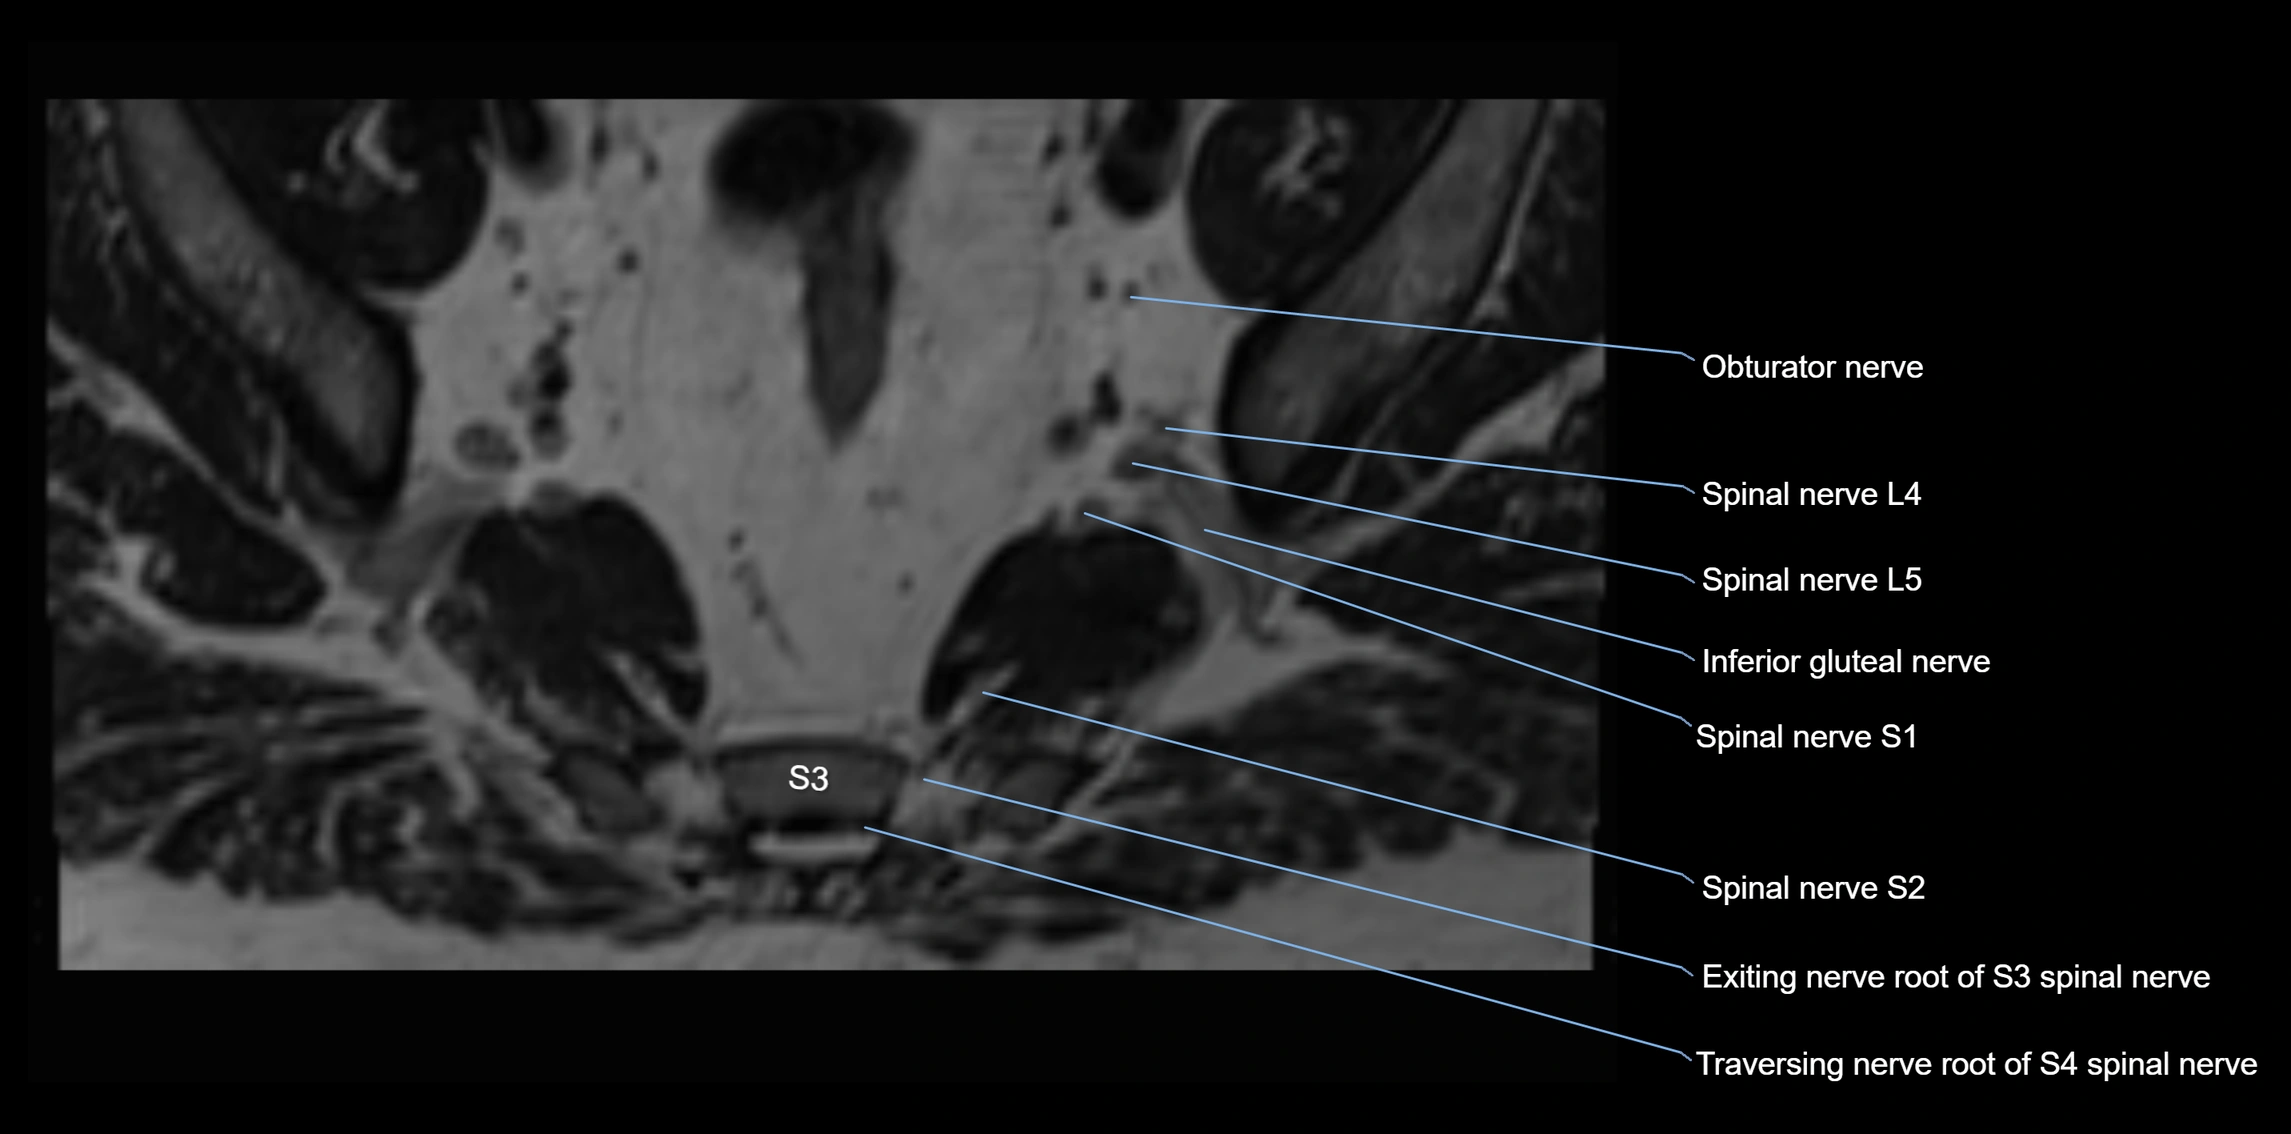

MRI image

image